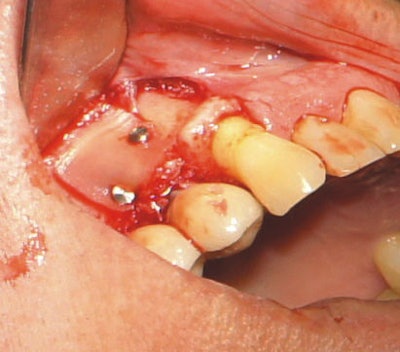

The procedure began with careful ablation of the affected area, which included hard and soft tissues, for several minutes intermittently. The implant surface of #5 was lightly brush-stroked with the laser beam and then the bony defect was forcefully ablated. Laser application was continued until the site was clean and visually free of granulation tissue.

Because of the laser's design, fast and precise cutting was easy to achieve, as ablation only requires adding more (for hard tissue) or less (for soft tissue) pressure to its variable-speed foot pedal. Additionally, the 9.3-µm wavelength allowed for simple removal of the edematous tissue while maintaining the integrity of the tooth. Healthy bone remained, and the implant surface was not significantly altered. The water mist permitted thorough cleaning of the site visually, which aided in predictability.

Another major advantage of laser dentistry in this case is improved disinfection. With its mist setting at 100%, this laser disinfects the implant surface, keeping it cool. Practitioners will also find that it promotes excellent perfusion from the bony crypt of the defect and bone bed of guided bone regeneration site.